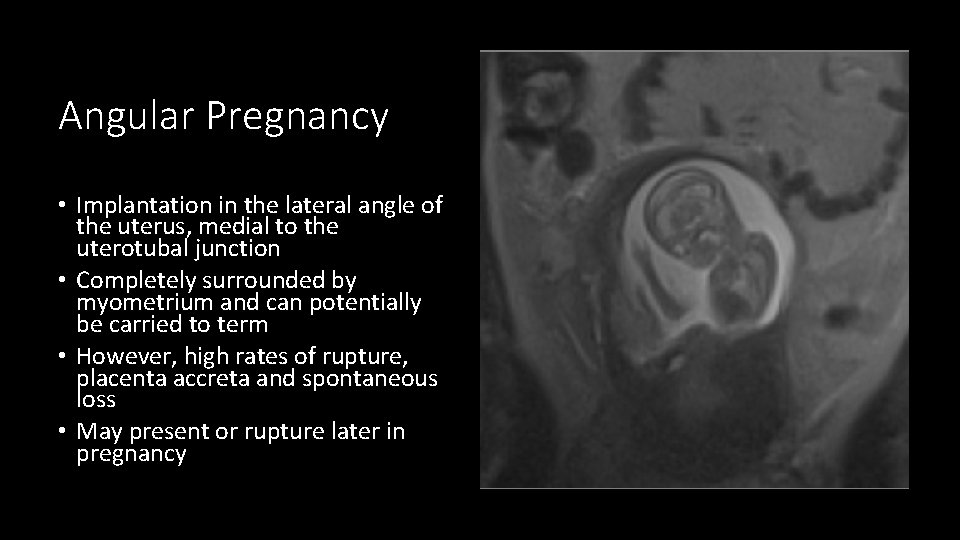

Angular Pregnancy • Implantation in the lateral angle of the uterus, medial to the uterotubal junction • Completely surrounded by myometrium and can potentially be carried to term • However, high rates of rupture, placenta accreta and spontaneous loss • May present or rupture later in pregnancy